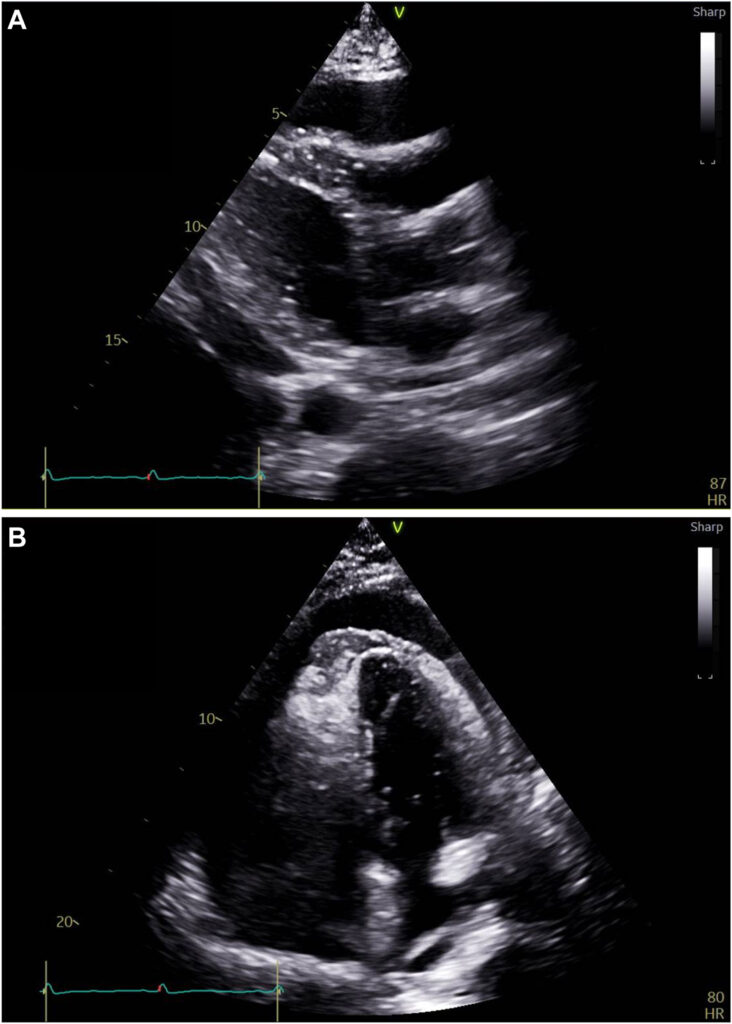

Um ecocardiograma foi novamente realizado e um importante derrame pericárdico foi documentado, contudo com aspecto multiloculado resultando em compressão de todas as 4 câmaras cardíacas.

Havia colapso diastólico da região apical e da parede lateral do ventrículo esquerdo, além do colapso do VD.

Também foi observado um espessamento do pericárdio (4 mm) com tethering da parede livre do VD e da parede lateral do VE caracterizado pela ausência da movimentação tipo deslizamento entre os folhetos parietal e visceral do pericárdio.